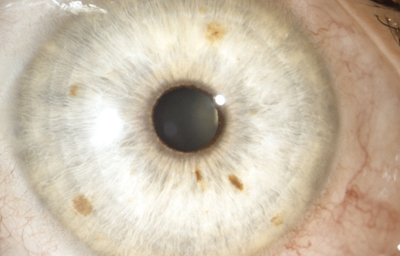

Hamartomas - Nódulos de Lisch. Son estructuras benignas, nodulares, de aspecto gelatinoso, implantadas con pedículo sésil sobre la superficie de la hoja anterior del Iris, compuestas por proliferación de células histológicamente maduras, de origen melanocítico normales del tejido en el que residen, de color que varía del castaño claro al castaño oscuro y generalmente de ± 1.0mm. Cuando se asocian a la Neurofibromatosis de Von Recklinghausen, se las considera patogneumónicas y se las denomina nódulos de Lisch (24, 25,26)

Hamartoma del Iris

Archivo Fotográfico Dr. Carmen Barraquer.

Nódulos de Lisch

Archivo Fotográfico Dr. Francisco Barraquer.

Nódulos de Lisch

Archivo Fotográfico Dr. Francisco Barraquer.